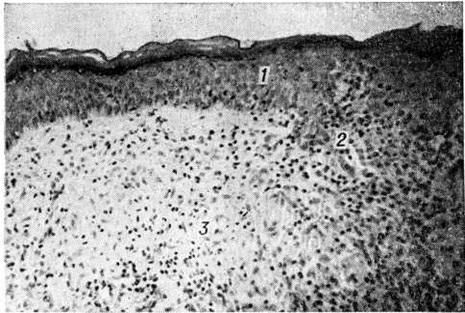

Рис. 1.

Микроскопическая картина лепроматозной гранулемы в коже: отчётливо видна свободная от инфильтрации субэпидермальная зона. Окраска гематоксилин-эозином; × 80. 1 — •эпидермис, 2 — субэпидермальная зона, 3 — инфильтрат.